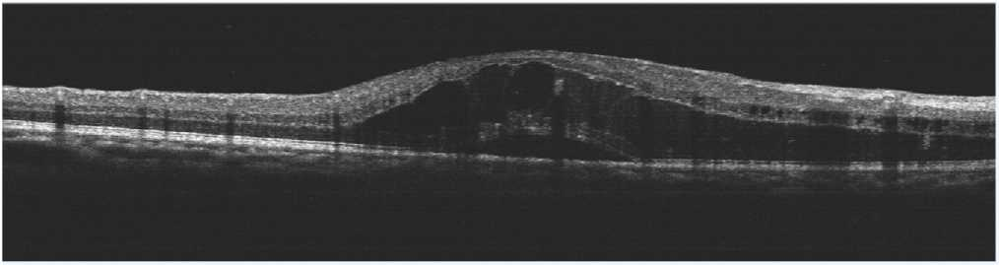

患者刘某,58岁,因右眼视力下降伴变形1月入院。既往有高血压病,血糖偏高病史,左眼视物不见10余年,经过眼科主治医师方霏的详细检查及眼底造影检查,发现是患上了右眼视网膜分支静脉阻塞,右眼黄斑水肿,左眼萎缩性黄斑病变。刘大叔入院时右眼视力仅0.1 ,需要使用一种新型的生物制剂(抗 VEGF)治疗,方霏主治医师向患者及家属交待病情、手术必要性及相关风险 ,在排除了手术禁忌症后,患者及家属表示同意手术治疗。次日,方霏主治医师在患者表面麻醉下进行右眼玻璃体药物注射术,术后患者无明显特殊不适。4周后复查,右眼黄斑水肿明显减轻,视力由0.1提高至0.6。玻璃体腔注药术明显改善了患者视力,患者刘大叔表示十分满意。

术前OCT检查提示右眼黄斑水肿

术后OCT检查提示右眼黄斑神经上皮层厚度较前明显变薄